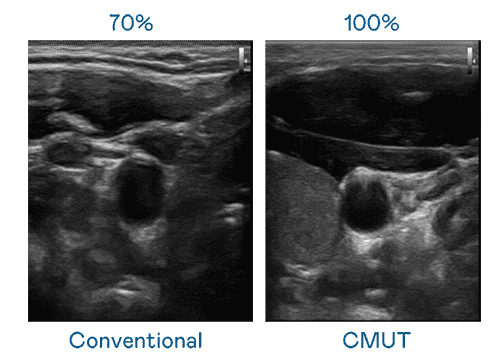

CMUT 技术是一种用电容式微机电元件来产生超音波讯号的技术。。。与传统 PZT 压电式技术相比,,,,CMUT 频宽增加 30%,,,,更宽频的超音波讯号让影像解析度大幅提升,,是实现高影像品质医疗超音波扫描、、、促进精准医疗发展的关键技术。。。

大频宽带来超清晰影像

超音波影像的解析度高低,,,,首先取决于探头能发出的讯号频宽。。。人生就是博 CMUT 可提供高清晰的超音波讯号,,,,提供高频宽、、、高灵敏度、、、影像纹理细节更高的超音波影像,,,协助医护人员缩短影像判读时间及利用精准的医疗影像进行诊断。。。